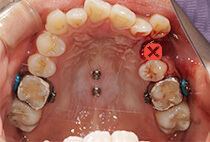

しっかり前歯を下げるために、インプラントアンカーを使用してコントロールしました。

治療前